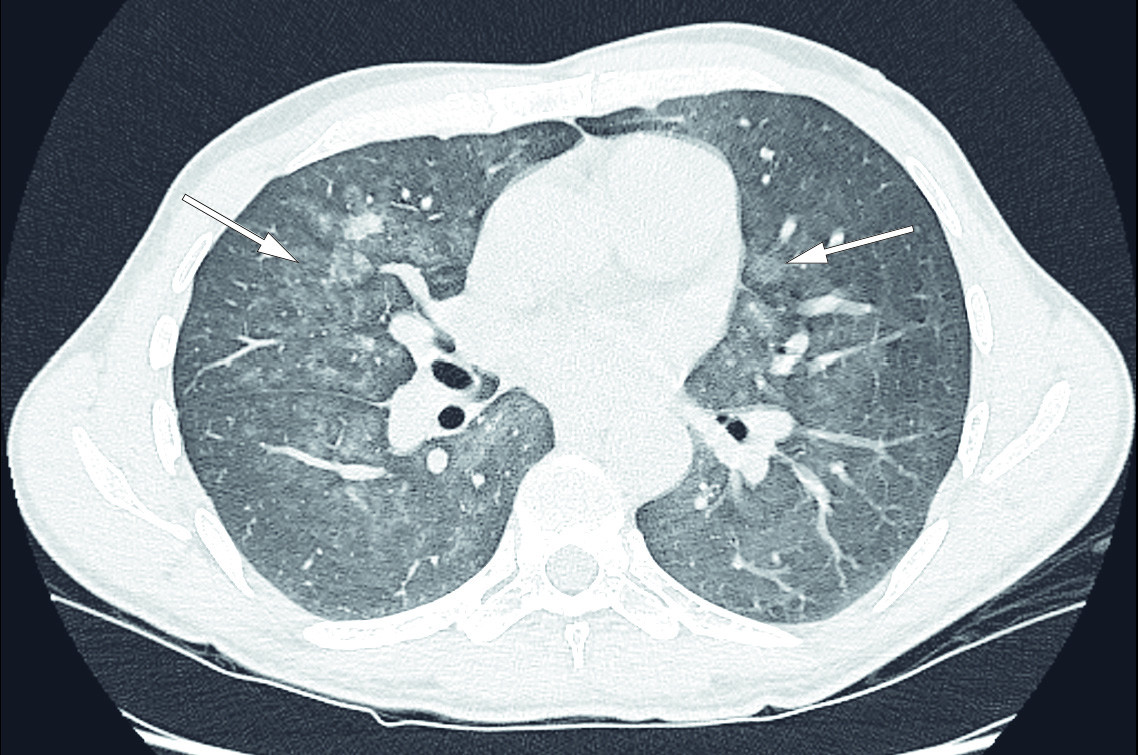

CT av brystkassen viste nå at det i løpet av fire uker var tilkommet bilaterale, flekkvise mattglassfortetninger med utsparing av lungetoppene og helt basale deler av lungene (figur 2). I tillegg til differensialdiagnosene beskrevet på PET-CT ble interstitielle sykdommer og blødning grunnet vaskulitt foreslått som differensialdiagnoser.